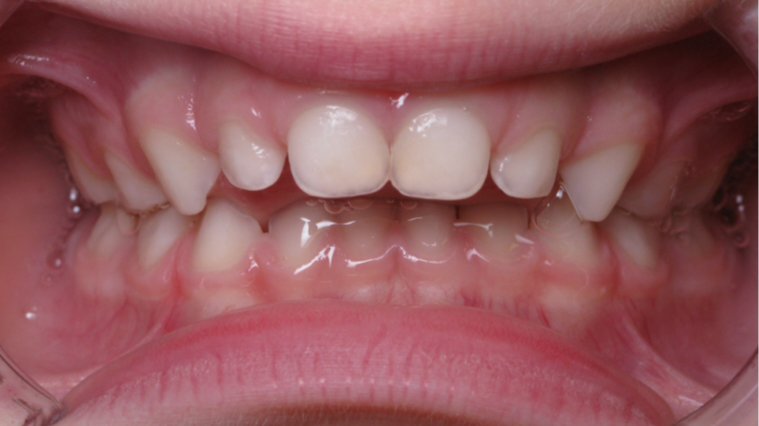

6 décalage sagittal 5 ans

Décalage entre les dents d avant en arrière

bilan début fin de traitement